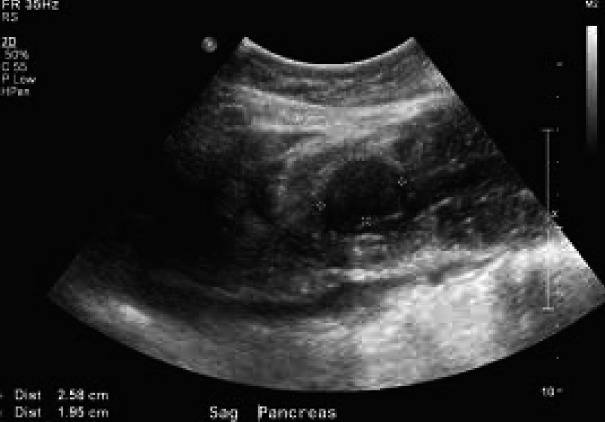

Abstract Image